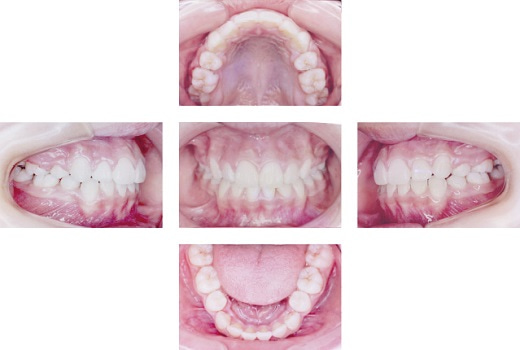

でこぼこが気になるという悩みから来院され、叢生を伴う上顎前突と診断。マルチブラケット装置を用いた治療を行い、2年3ヶ月で矯正治療が終わりました。

| 治療内容 | マルチブラケット装置 |

|---|---|

| 治療期間・回数 | 2年3ヶ月/27回 |

| 費用※自由診療となります。 | 1,083,500円(税込) |

| リスク・副作用 | ・装置が付くと装置に擦れて口内炎が出来やすくなる ・歯が動くときに痛みがでることがある ・装置が付くと歯みがきが難しくなるため虫歯や歯肉炎につながりやすい ・患者様に協力していただけないことがあると治療が進まない事がある ・治療後、保定装置(リテーナー)を指示通り入れないことや、その他の指導内容が守れない場合、後戻りする可能性があること ※上記の内容は個人差があり、全ての方に当てはまるものではございませんので参考としてご覧ください。 |